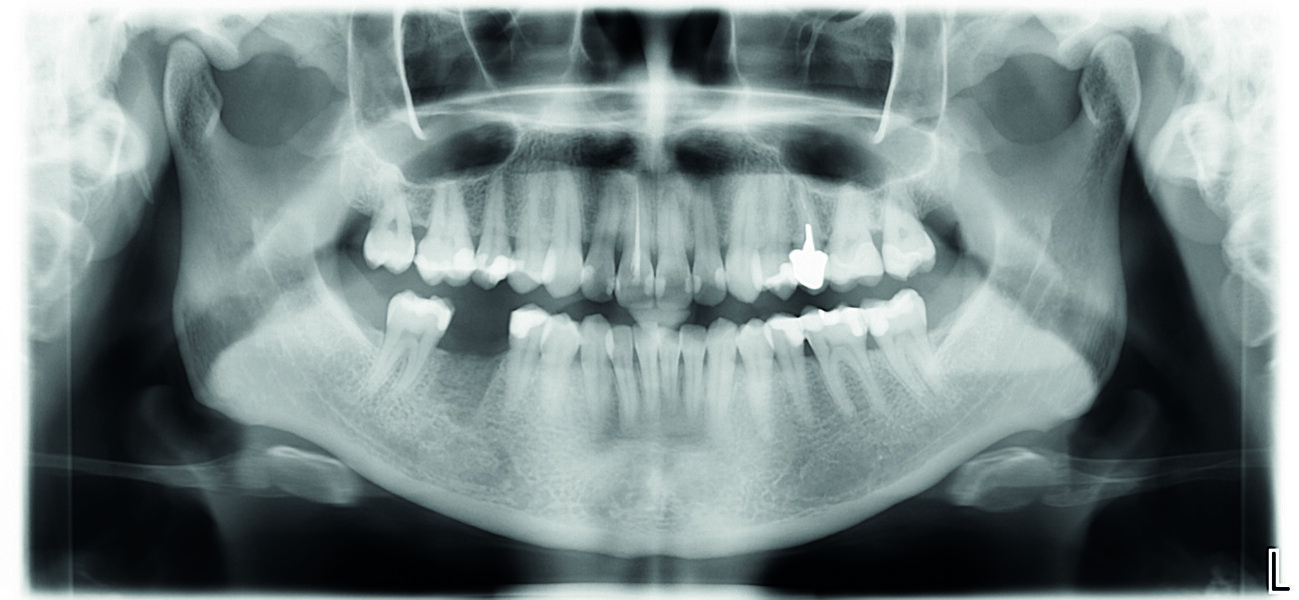

À l’issue de l’intervention, vérification de la correspondance entre la planification et la chirurgie avec une rétroalvéolaire (Figs. 11 et 12).

Fig. 12 : Radiographie de contrôle postopératoire de l’implant en 46.

Fig. 13 : Radio panoramique de contrôle postopératoire.